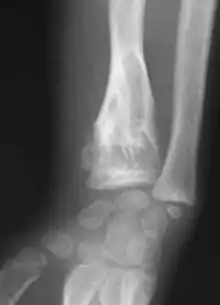

X-ray image showing enchondromas localized in the lower part of the radius of a 7-year-old girl with Ollier disease.

Abnormal bone growth such as shortening or thickening and deformity may be observed in patients of Ollier disease. These bone lesions are visible at birth using radiography but are usually not screened or examined for until clinical manifestations present during early childhood. However, some patients may exhibit no signs of any symptoms.[1] One study found thirteen to be the mean age of diagnosis in patients with Ollier disease. In an X-ray, there would normally be the presence of several homogeneous lesions of an oval or elongated shape with bone edges that are slightly thickened.[3] With age, these lesions may calcify and appear as diffusely minute spots or stippled. Fan-like septations or streaks would be indicative of the presence of several enchondromas. Early detection and consistent and repeated monitoring is important in order to prevent and treat any potential bone neoplasms.